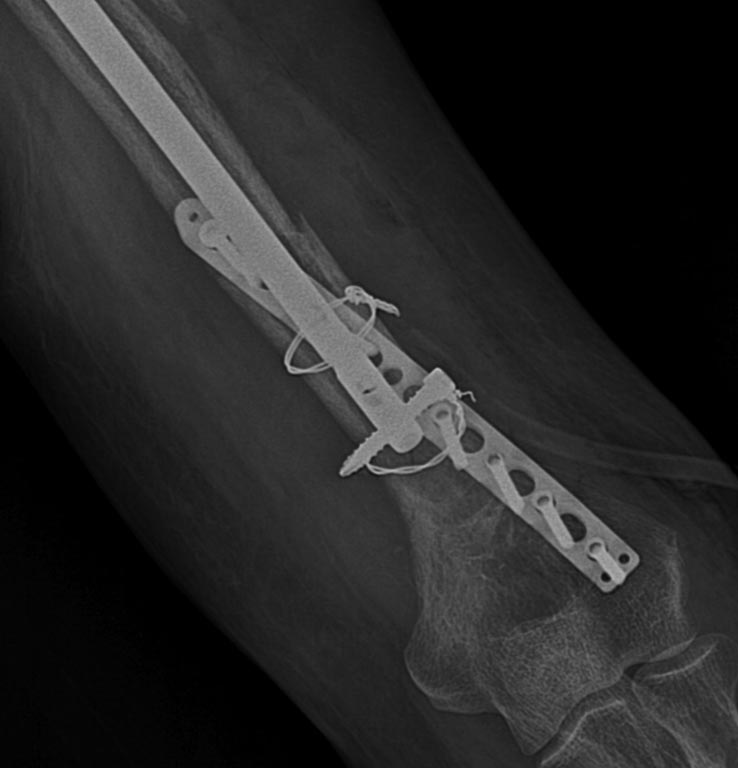

[Ortho] перелом плеча на гвозде

Rg